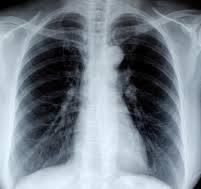

Radiografía de tórax: índice cardiotorácico normal, hilios engrosados con adenopatías calcificadas. Silueta cardiomediastínica y parénquimas sin otros hallazgos.